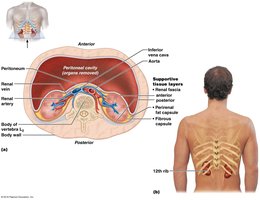

The kidneys are retroperitoneal organs located in the abdominal cavity, protected by connective tissue and adipose layers. Each kidney contains about 1.2 million nephrons, the functional units responsible for urine formation.